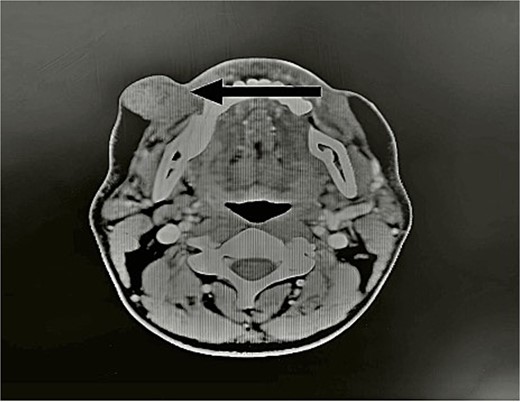

Computed tomography showed a round tumor under the skin, lateral to the buccinators muscle and anterior edge of the masseter muscle (Fig. 2).

CT scan showed the tumor (arrow). Axial view of head CT scan revealing a mass above the right parotid gland.